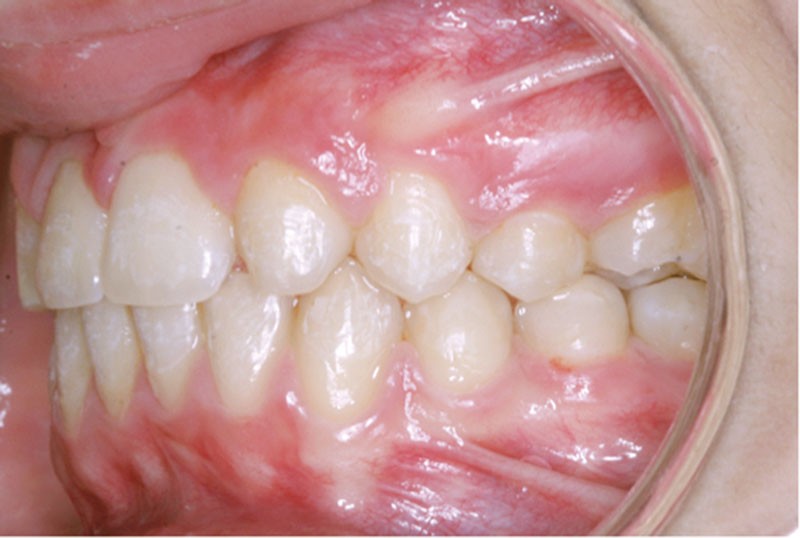

Ludivine T. âgée de 12 ans et demi présente une agénésie des deux incisives latérales maxillaires dans un contexte occlusal de classe II division 2 (fig. 1 à 3).

Les vues endo-buccales (fig. 2) montrent la classe II division 2 occlusale associée à une forte supraclusion incisive et l’évolution spontanée de 13 et 23 pratiquement en place de 12 et 22. Il persiste cependant un diastème disgracieux entre 13 et 11.